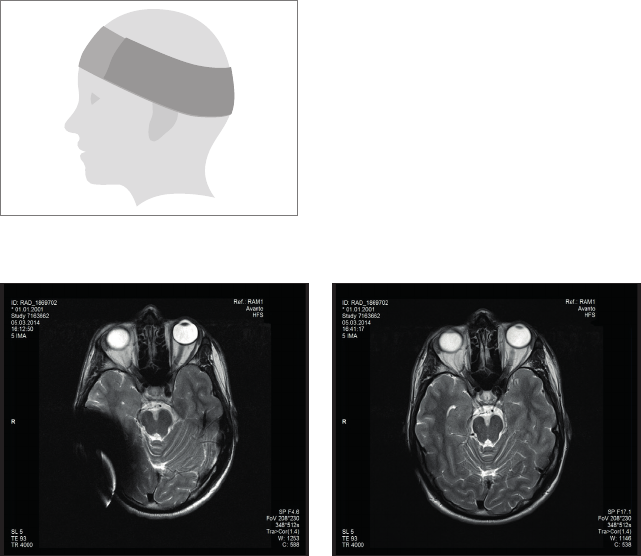

Safety Guidelines:

• Before patients enter any MRI room all external components of the implant system audio

processor and accessories) must be removed from the head. For field strengths of . T

and T, a supportive head bandage must be placed over the implant. A supportive head

bandage may be an elastic bandage wrapped tightly around the head at least three times

(refer to Fig. A). The bandage shall fit tightly but should not cause pain. Performing an

MRI without head bandage could result in pain in the implant area and in worst case can

lead to migration of the implant and/or dislocation of the implant magnet.

Fig. A Head bandage to support xation of the implant